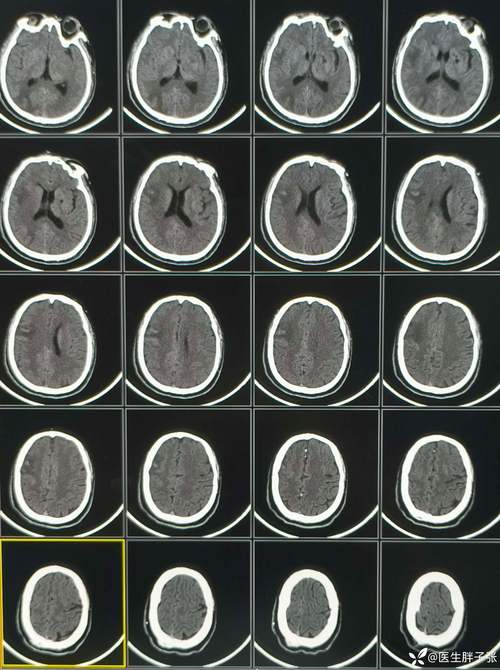

(图片来源网络,侵删)

一旦影像学检查(通常是CT或MRI)发现“中线结构移位”,神经外科和神经内科医生会立刻采取一系列紧急措施,目标只有一个:降低颅内压,挽救生命。

(图片来源网络,侵删)严密监测血压、心率、血氧饱和度等生命体征,维持生命体征稳定。